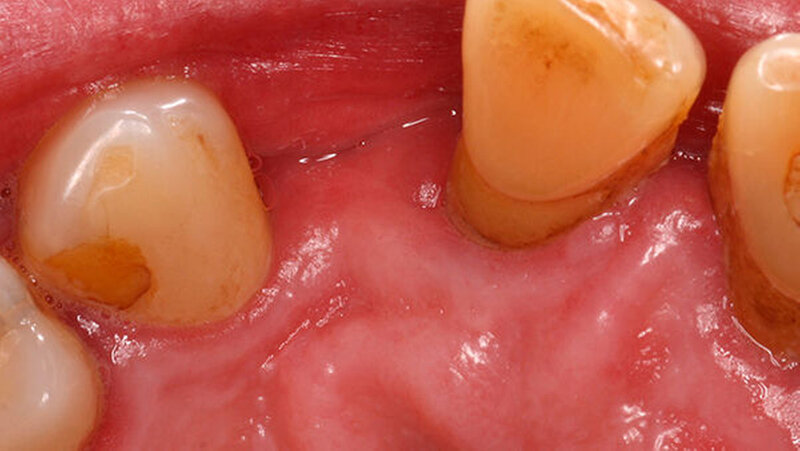

Für eine konventionelle brückenprothetische Versorgung scheiden die Schneidezähne ebenfalls aus: Zum langfristig prognostisch sicheren Ersatz des 22 wären Extraktionen und mehrere Substanz-opfernde Präparationen unausweichlich. Aufgrund des hohen Patientenalters und des Ausscheidens klassischer prothetischer Rehabilitationsmaßnahmen wird die Frontzahnlücke mit einer Adhäsivbrücke aus Metallkeramik versorgt (Abbildungen 3 und 4).

Durch die parodontal bedingte Elongation von 11 und 21 musste ein Kompromiss hinsichtlich der Gestaltung des Brückengliedes 22 im Hinblick auf dessen inzisale Ausdehnung erfolgen, so dass nun 23 kürzer ist als 22 (Abbildung 5). Ein halbes Jahr später befindet sich die Restauration unverändert in situ.